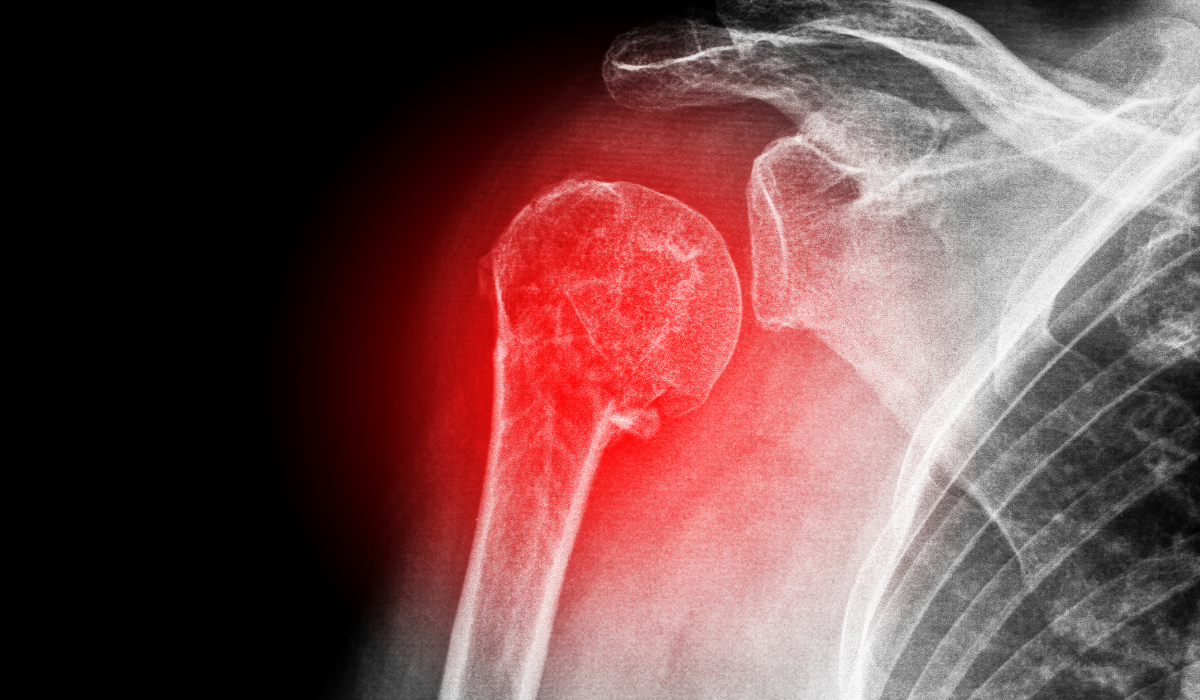

Shoulder Dislocation

A dislocated shoulder is a shoulder sickness that takes place while the ball of the higher arm bone comes out of the shoulder socket. In this circumstance, the anterior ligaments withinside the shoulder tear and reason ache and lack of characteristic withinside the affected arm.

In a few sufferers the ball (humeral head) comes out of the socket (glenoid), a circumstance known as dislocation. It is related to extreme ache and the incapacity to transport the shoulder. It can also additionally take place because of damage to the shoulder in the course of falls, avenue visitors accidents, or at the same time as gambling sports activities.